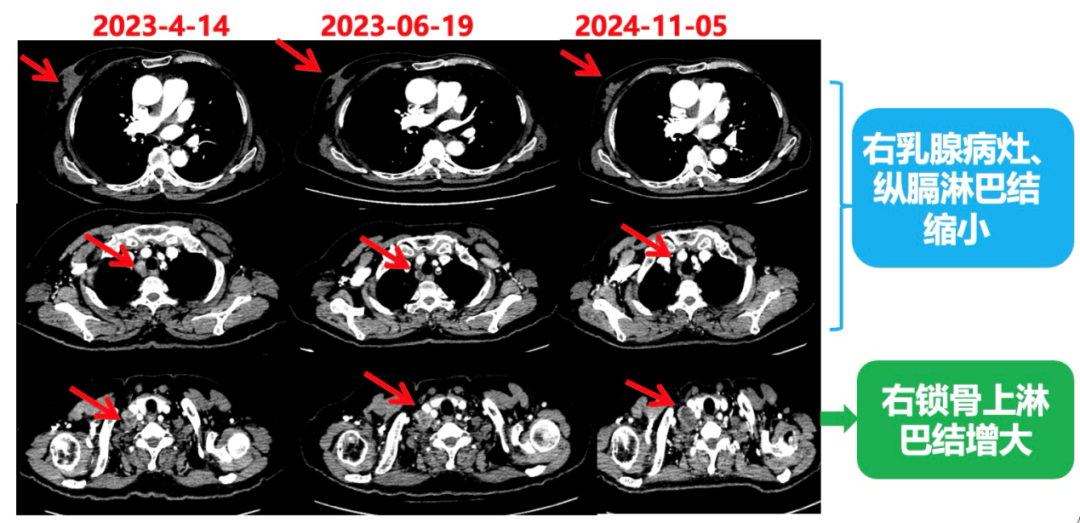

1.右乳外上象限乳腺癌病灶(22*16mm),对比2023-04-14 CT(26*24mm)较前缩小,FDG代谢活跃。右侧腋窝小淋巴结(5mm),较前稍缩小,代谢不活跃。右侧锁骨上区、上纵隔淋巴结转移瘤(24*18mm),现大小同前相仿,代谢活跃(SUV:6.7)。

2024-11-5复查CT:右乳外上象限占位(11mm×9mm),较前明显缩小;上纵隔及右肺门多发淋巴结转移缩小;右锁骨上区淋巴结较前增大。余部位未见肿瘤转移及复发征象。